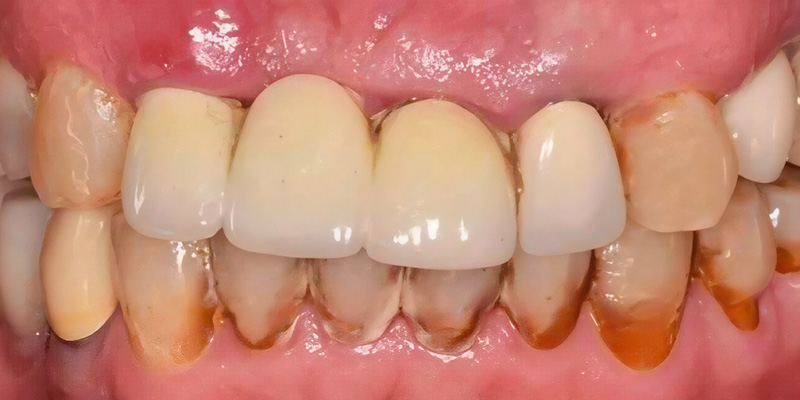

Un patient de 67 ans s’est présenté après avoir perdu deux fois son bridge au maxillaire antérieure. Il recherchait une solution fixe avec une meilleure esthétique et a été adressé par son praticien habituel pour un traitement implantaire.

Fig. 1 : Vue préopératoire antérieure.